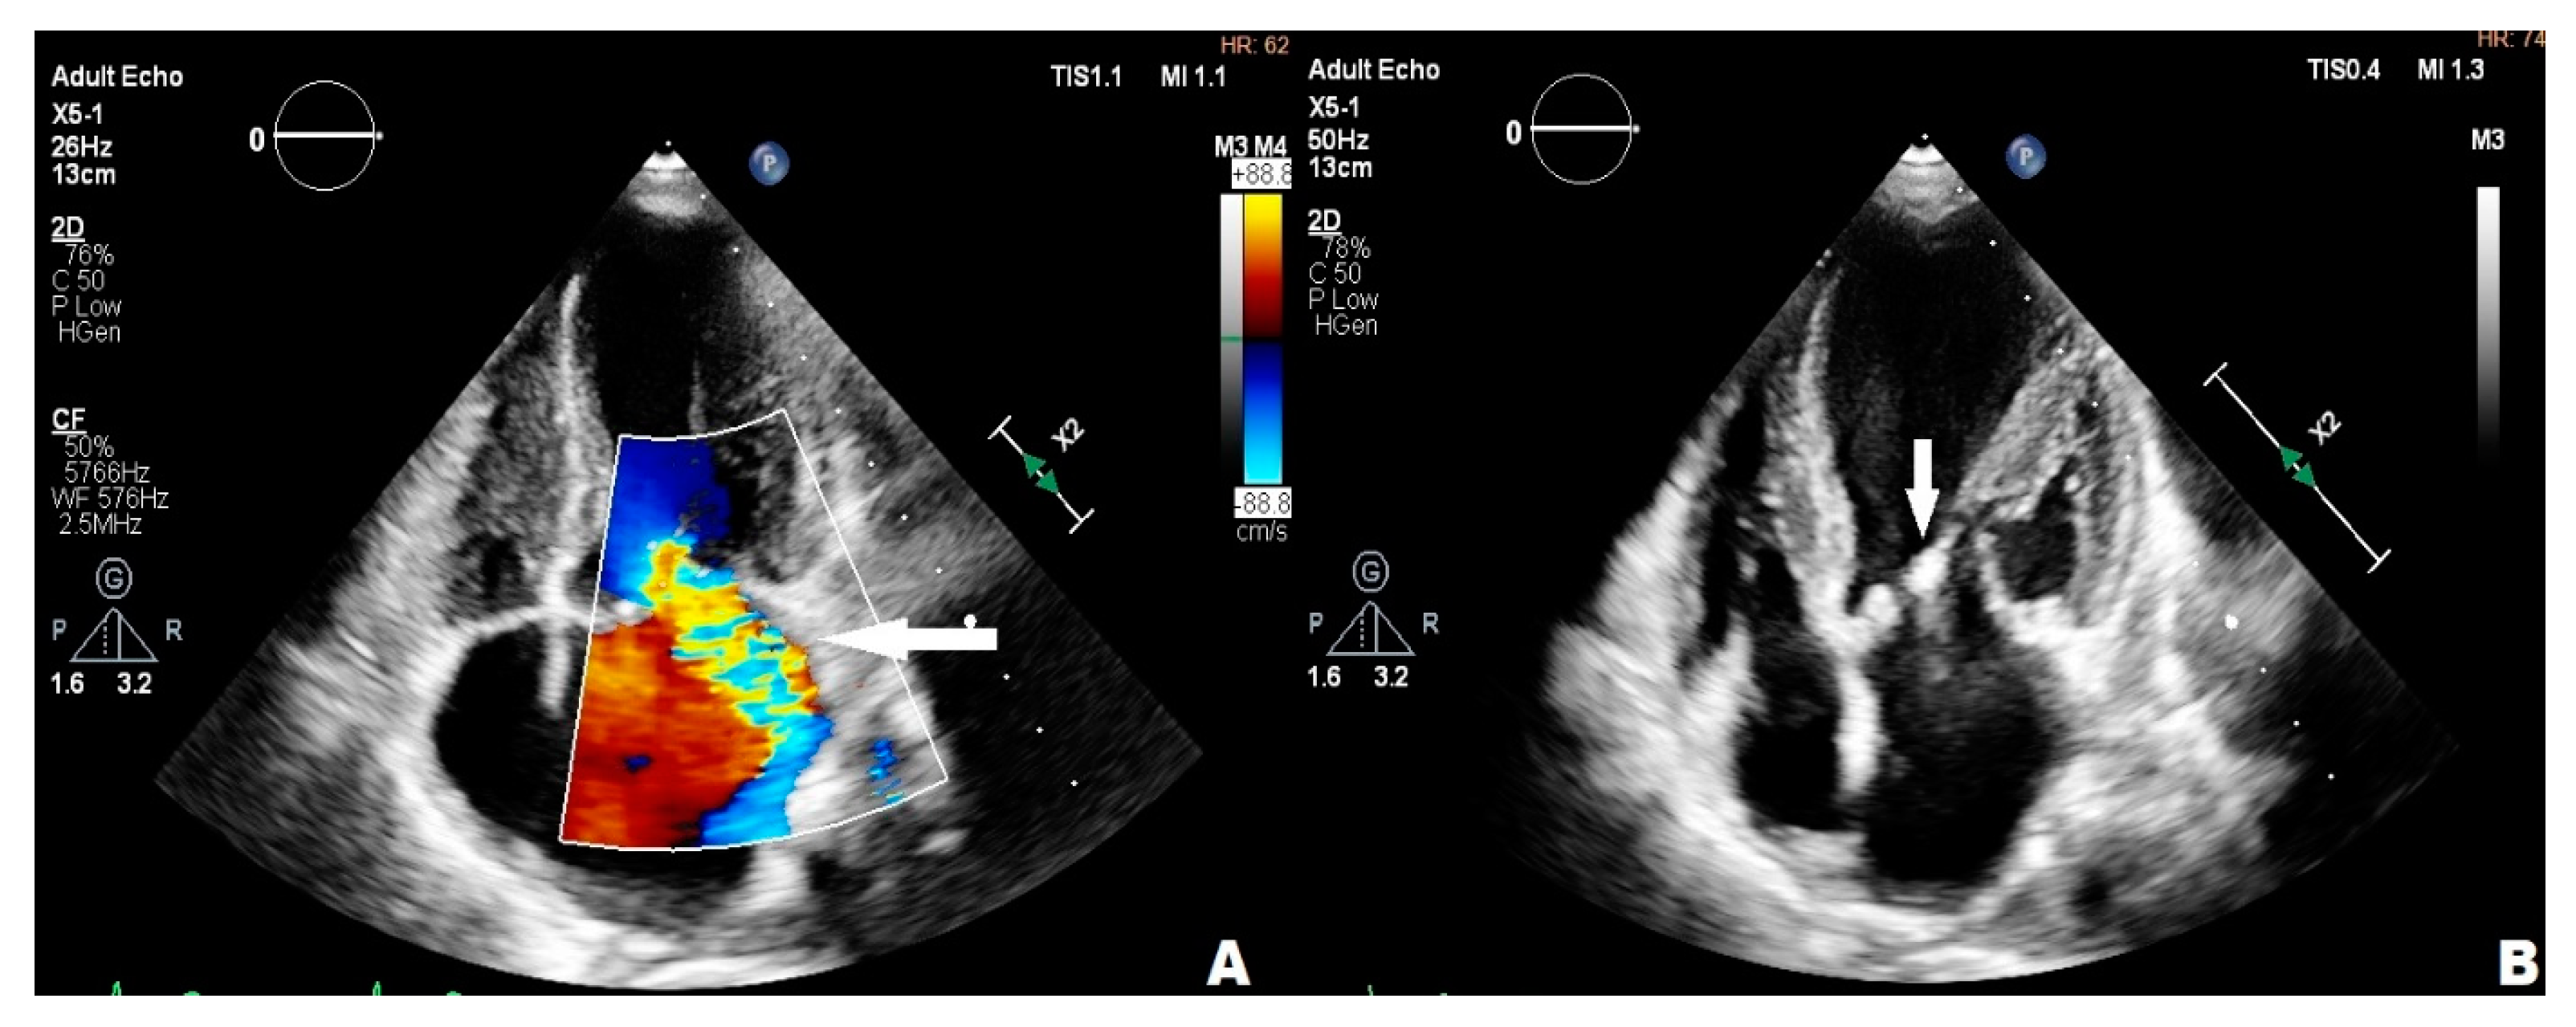

3.2. Case 2